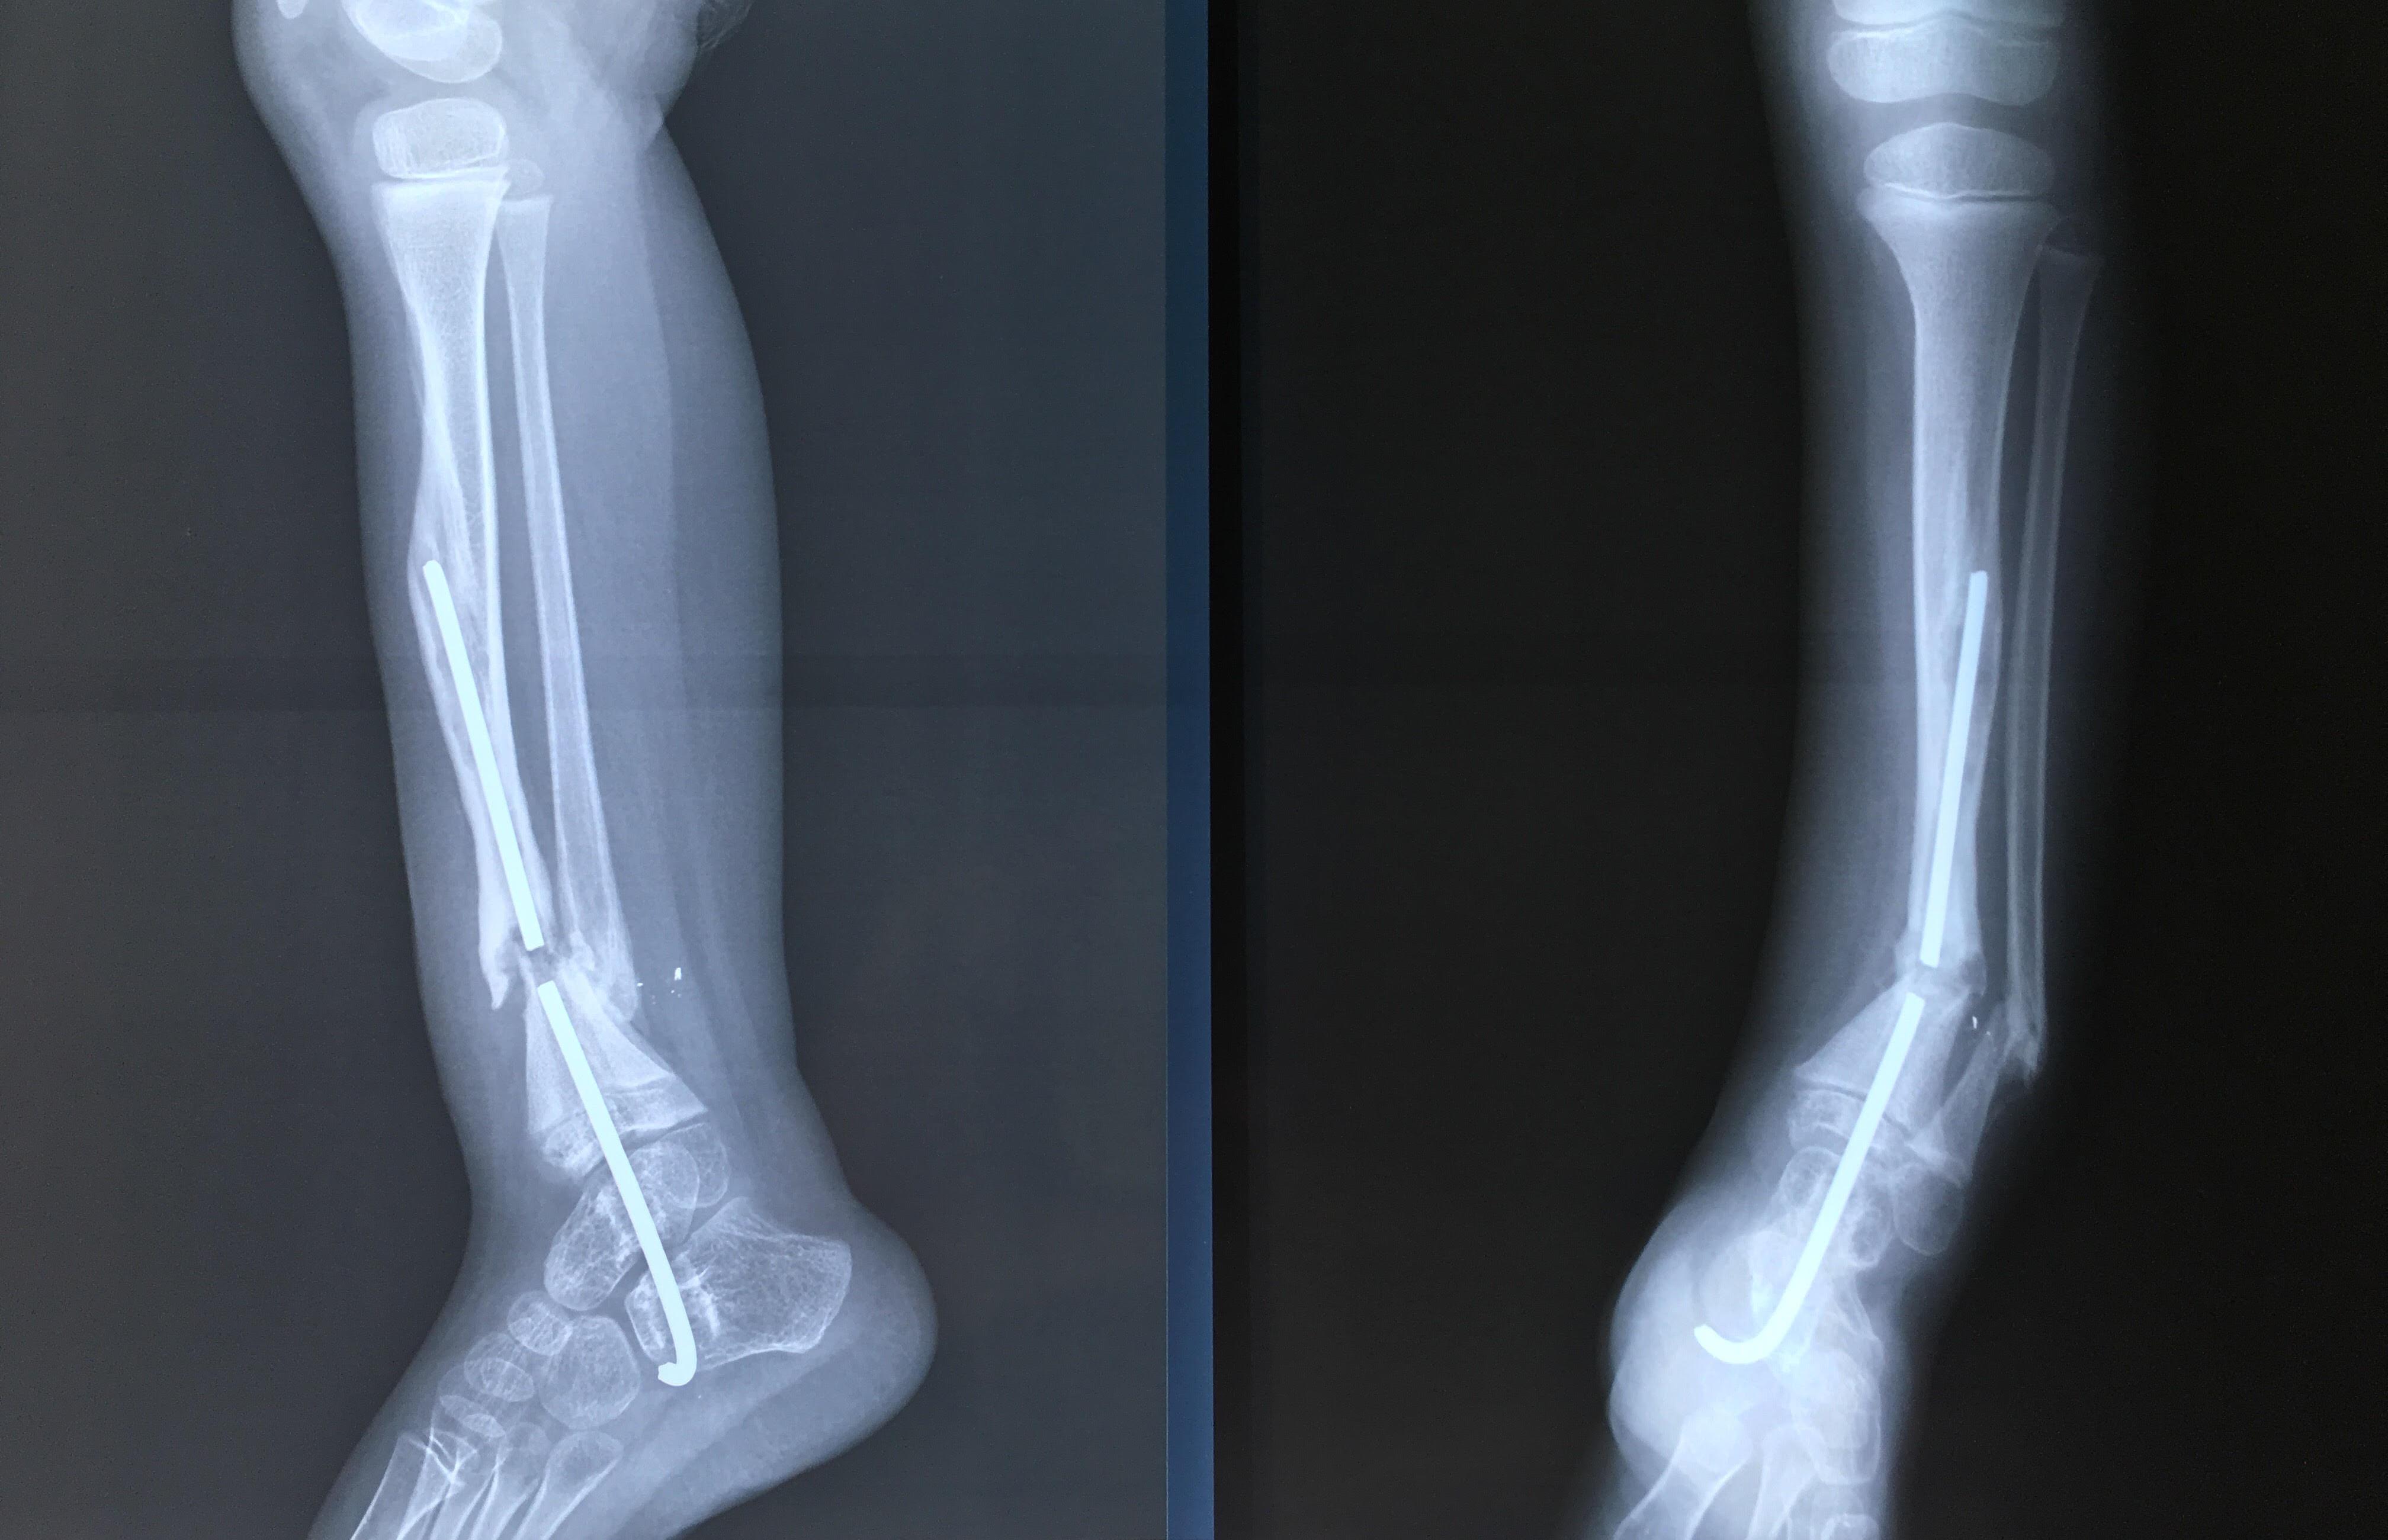

Phẫu thuật thành công ca bệnh hiếm gặp...khớp giả bẩm sinh xương chày

26/06/2019 17:00

Đã xem: 3703

Bệnh viện Chấn thương- Chỉnh hình Nghệ An, vừa phẫu thuật thành công cho bệnh nhi khớp giả bẩm sinh xương chày